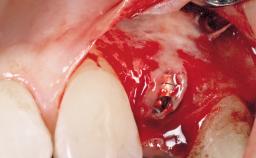

Surgical treatment of a 32-year old, healthy and non-smoking female who required removal and replacement of a lateral maxillary incisor due to internal root resorption. The inflammatory process caused a reduction of the crestal bone level on the distal side of the tooth necessitating an augmentation procedure to meet the patient's high esthetic demands. Due to the high smile line, the thin soft-tissue biotype and triangular-shaped teeth several esthetic risk factors are present.

After flapless tooth removal and a healing period of 6 weeks a diameter-reduced two-piece implant is placed. The bone defect on the facial aspect is corrected with a contour augmentation using autologous bone chips covered with DBBM particles and a collagen membrane according to the Guided Bone Regeneration (GBR) approach.